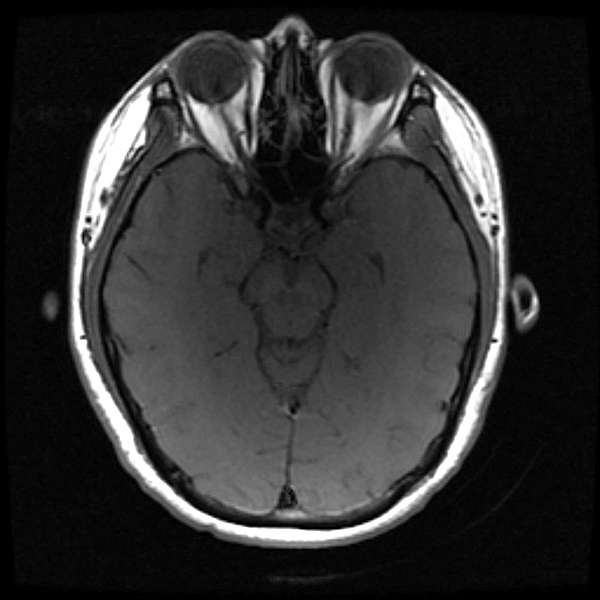

once i got back home and checked out my scans in osirix (the mac os x application to view DICOM medical imaging slides), i was blown away. talk about invasive: you haven't seen intimate until you've looked at photos of the inside of your body. the coolest part is since the scans were done in cross-sections, i can animate the scans so it looks like the beam is passing through my neck and head (all 800+ images). i've always known that inside my body was all sorts of muscles and veins and organs, but i guess i was hoping for something less messy, maybe circuit boards and memory chips instead. i know MRI's were first used in the late 60's, but this is my first time experiencing the technology in-person and it's pretty amazing. talk about futuristic! to be able to see with so much detail the insides of my body without having to cut me open! if scientists can do this, what else can they do? my only regret is they only imaged me from my shoulder up. i'd love to have a full-body scan. maybe i can fake some sort of internal injury and get my doctor to okay the procedure. i recommend anyone who's never had an MRI done to do so when they have the chance.

speaking of doctors, the main reason why i was at MGH this morning was for a follow-up appointment with my doctor. he basically told me that my MRI scans were fine as well as my blood work (he wrote me a letter a few weeks ago, so i already knew the news). since the pain in my neck had already disappeared,